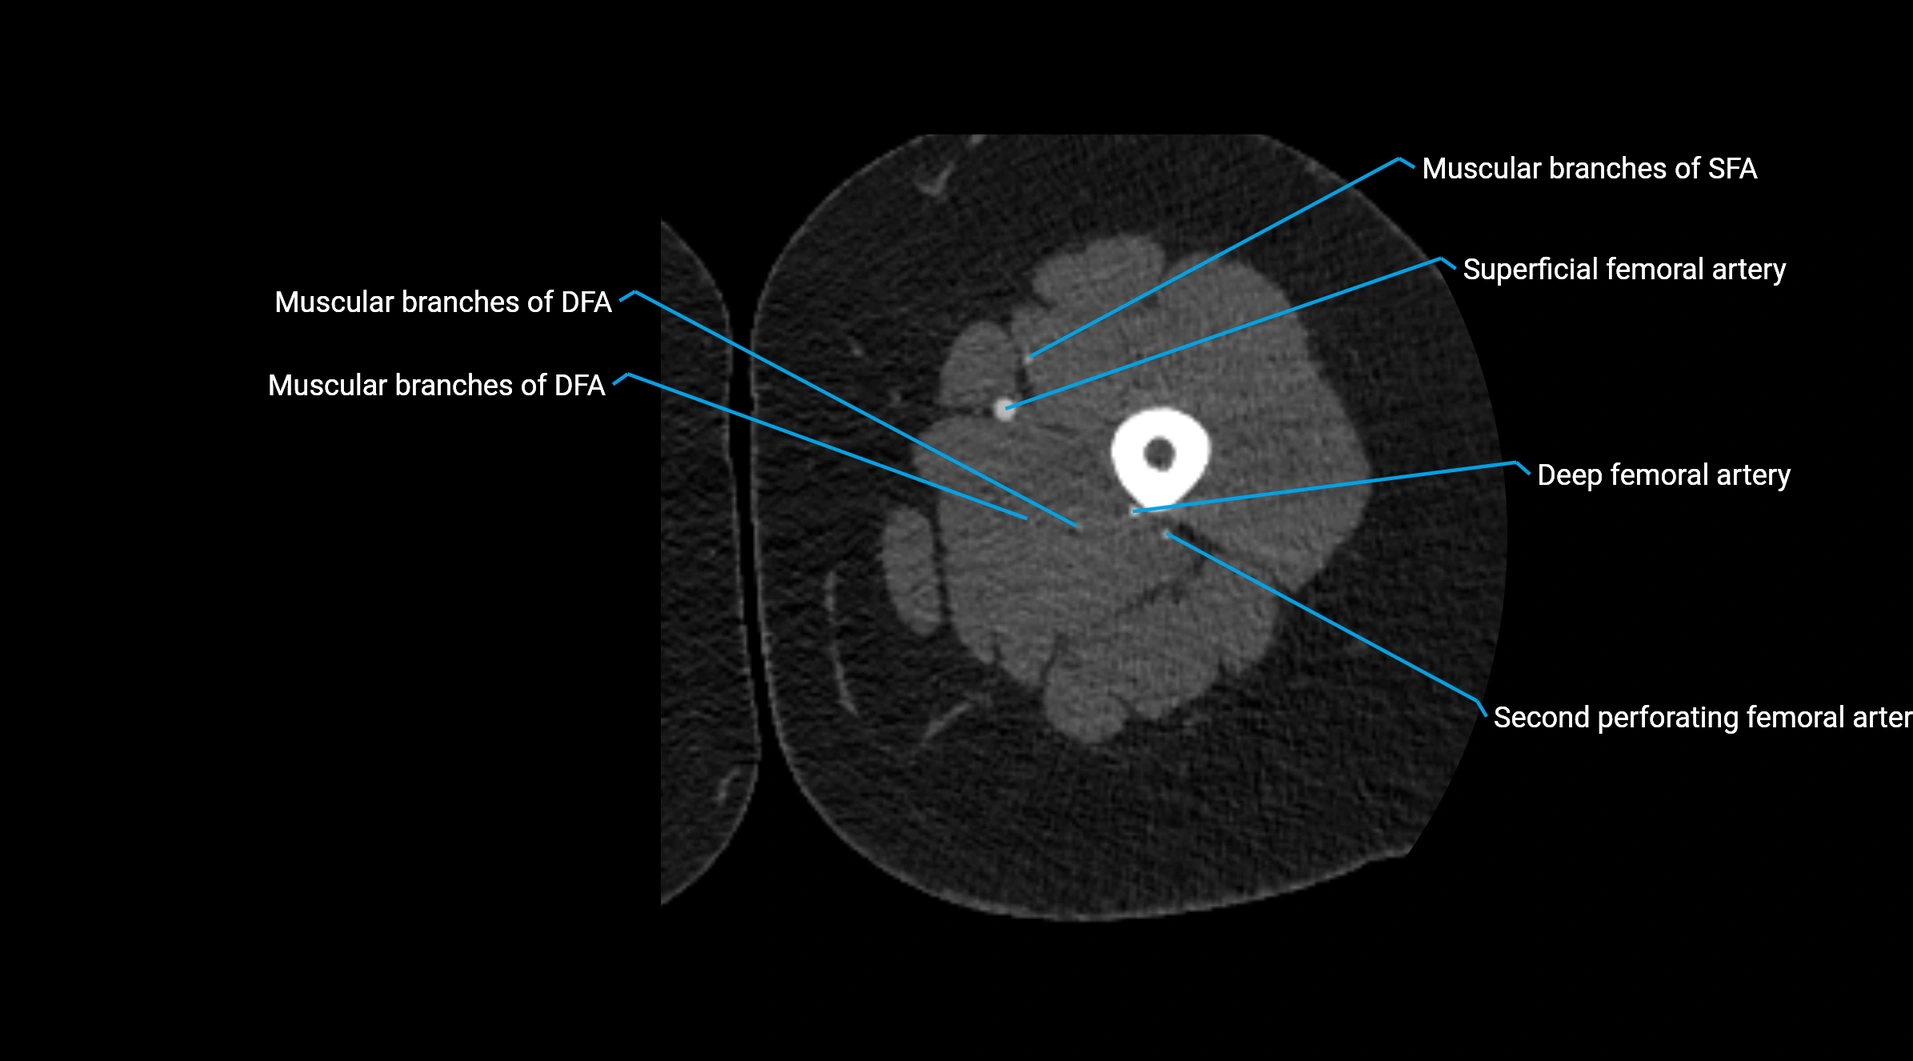

CT images

image